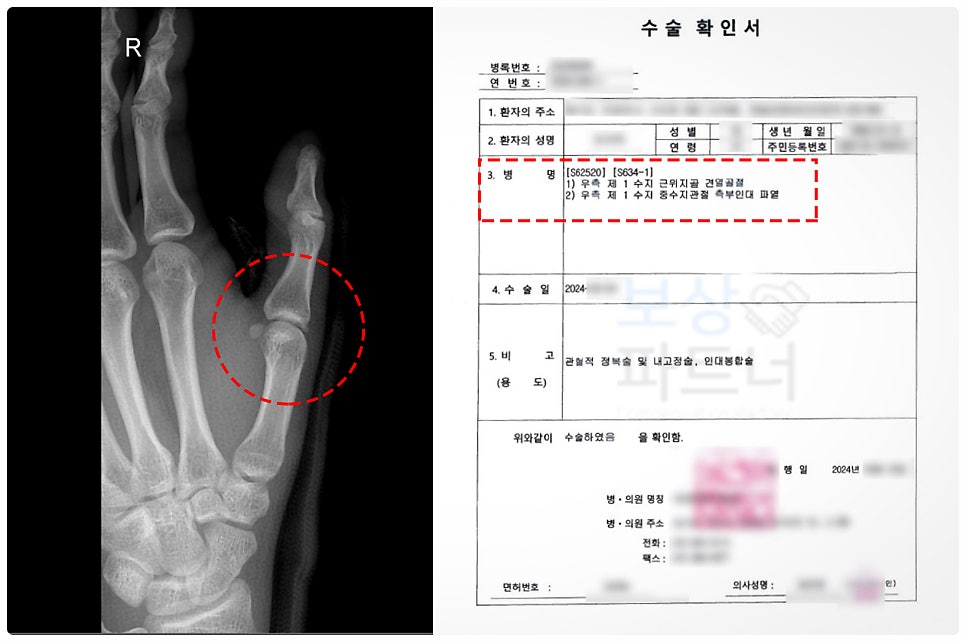

진단명 :

우측 제1수지 근위지골 견열골절 [S62520] 중수지관절 측부인대 파열 [S634-1]

치료 내용 :

관혈적 정복술 및 내고정술, 인대봉합술

견열골절(avulsion fracture)이란 뼈의 일부가 힘줄이나 인대에 의해 강하게 잡아당겨져, 작은 조각으로 떨어져 나가는 골절을 말합니다. 피해자께서도 이러한 견열골절로서, 엄지가 꺾일 때 인대가 뼛조각을 당기면서 같이 떨어져 나간 상태였습니다.

견열 골절의 특징은 관절 근처에서 자주 발생하며, 보통 인대 손상과 동반되는 경우가 많습니다. 그리고 엑스레이 상으로 작은 뼛조각이 떨어져 나간 모습이 확인되며, 향후 운동기능 제한이 생길 가능성이 있습니다.